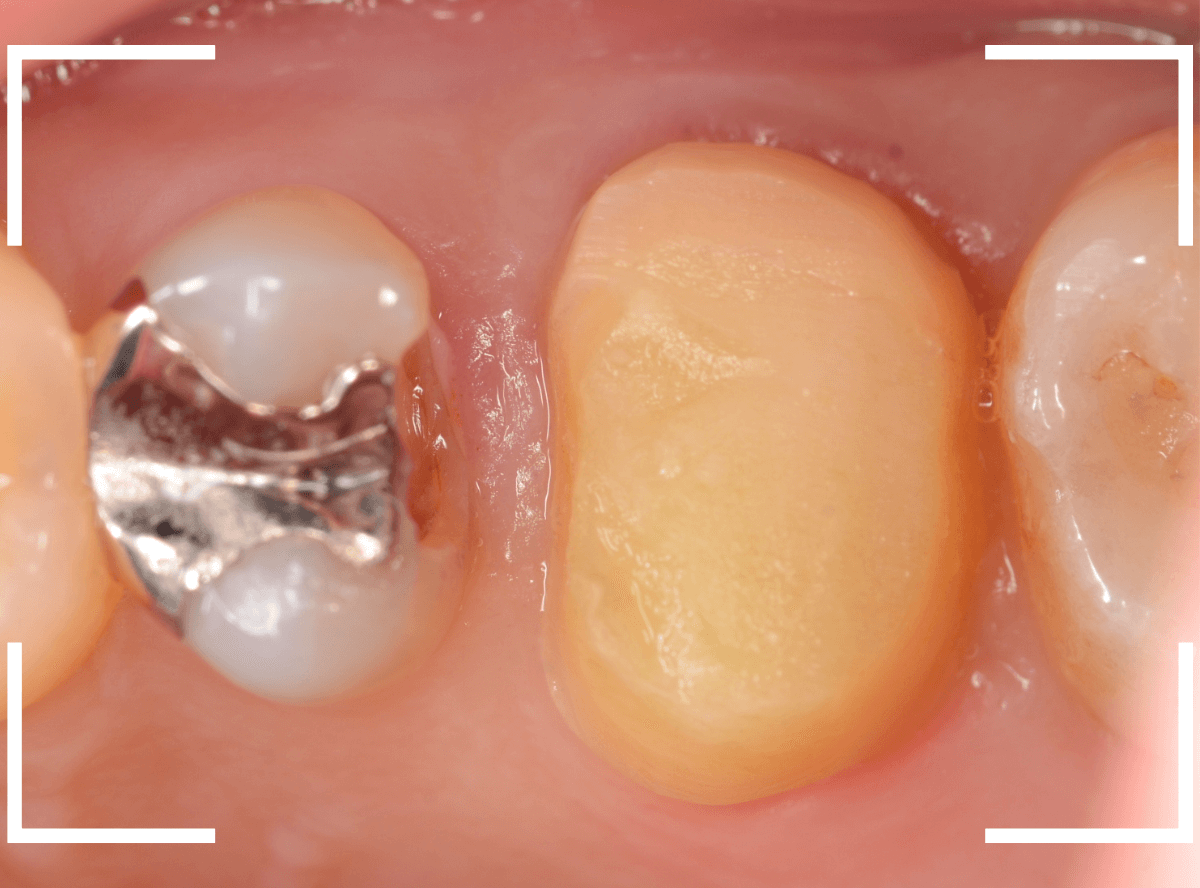

「上の奥歯の銀歯を白くやり替えたい」というご希望の患者さんです。

検査の結果、再製に問題なさそうでしたので、ジルコニア・クラウンで再製作する治療を進める事になりました。

メタル・クラウンを外すと、奥の歯の虫歯が見つかりました。

奥歯はおやしらずなので、抜歯も選択肢になるのですが、特にご希望されなかったため、一緒に虫歯の治療をすることになりました。

さし歯の土台の補修と、おやしらずの虫歯の処置をしたところです。

この状態で型をとります。

治療前後の比較写真になります。